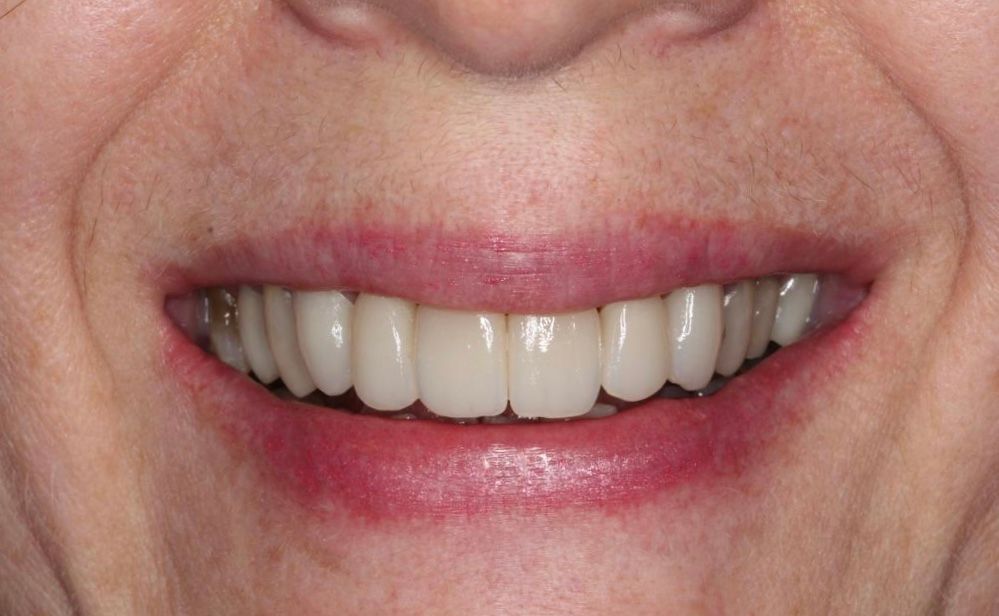

La especialidad en prótesis Bucal se enfoca en rehabilitar mediante prótesis unitarias, múltiples o totales la función masticatoria de nuestros pacientes brindándoles una mejor estética dental, confort, anatomía dental y función.

La evaluación es integral y multidisciplinaria, teniendo como objetivo una atención humana de calidad, ética, profesionalismo y calidez